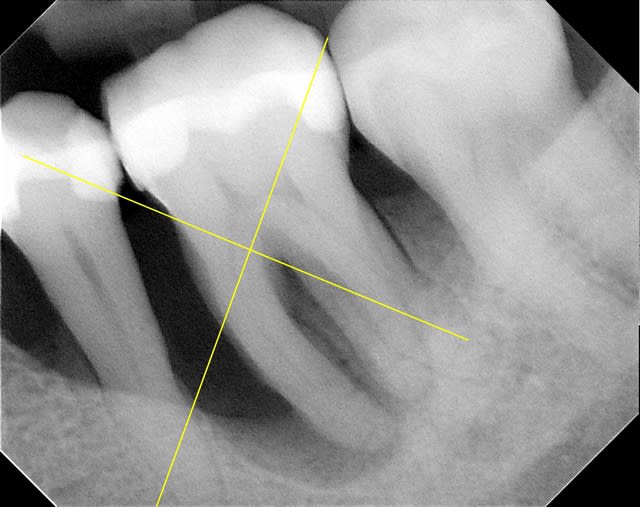

oui, Noah,voici les radiographies de ce patient

j'ai fait un p'tit détour au cab.

merci

flicfac, en ce qui concerne la 46, tu as d'après ton bilan de sondage une atteinte de furcation de grade III, ce qui signifie que ton potentiel de régénération est nul.